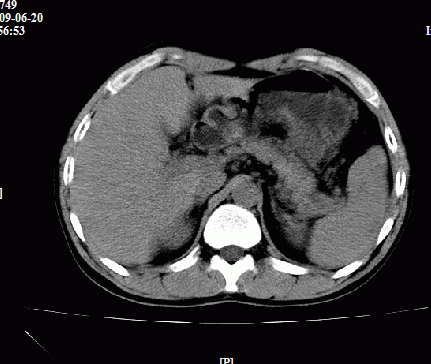

以下是引用随光逐影在2009-6-23 11:37:00的发言:[br]1)考虑胃癌;建议行胃镜检查进一步明确诊断。2)肝右叶肝内胆管结石(或钙化)。

以下是引用zxl51642在2009-6-23 11:31:00的发言:[br]胃大弯侧壁明显增厚呈软组织肿块,考虑胃癌可能性大,建议胃镜活检。